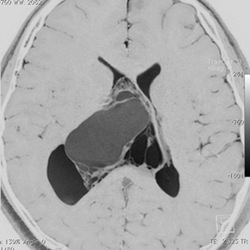

20代の男性の神経細胞腫です。側脳室の中のとても大きな腫瘍です。上段はガドリニウムという造影剤を入れた時のMRIです。下段の中央はCTですが,石灰化が見られます。脳外科の先生には,この脳室内腫瘍は一見transcallosal approach(経脳梁到達法)という手術で取れるように見えるかもしれませんが,そうではなくて,脳室の壁とくに上壁と側壁にくっついているのでなかなか取れません。この患者さんの場合は右の頭頂葉というところからtranscortical approach(経皮質到達法)で全摘出しました。後遺症もなく再発もなく術後10年が過ぎています。全部とれれば治ってしまう腫瘍です。